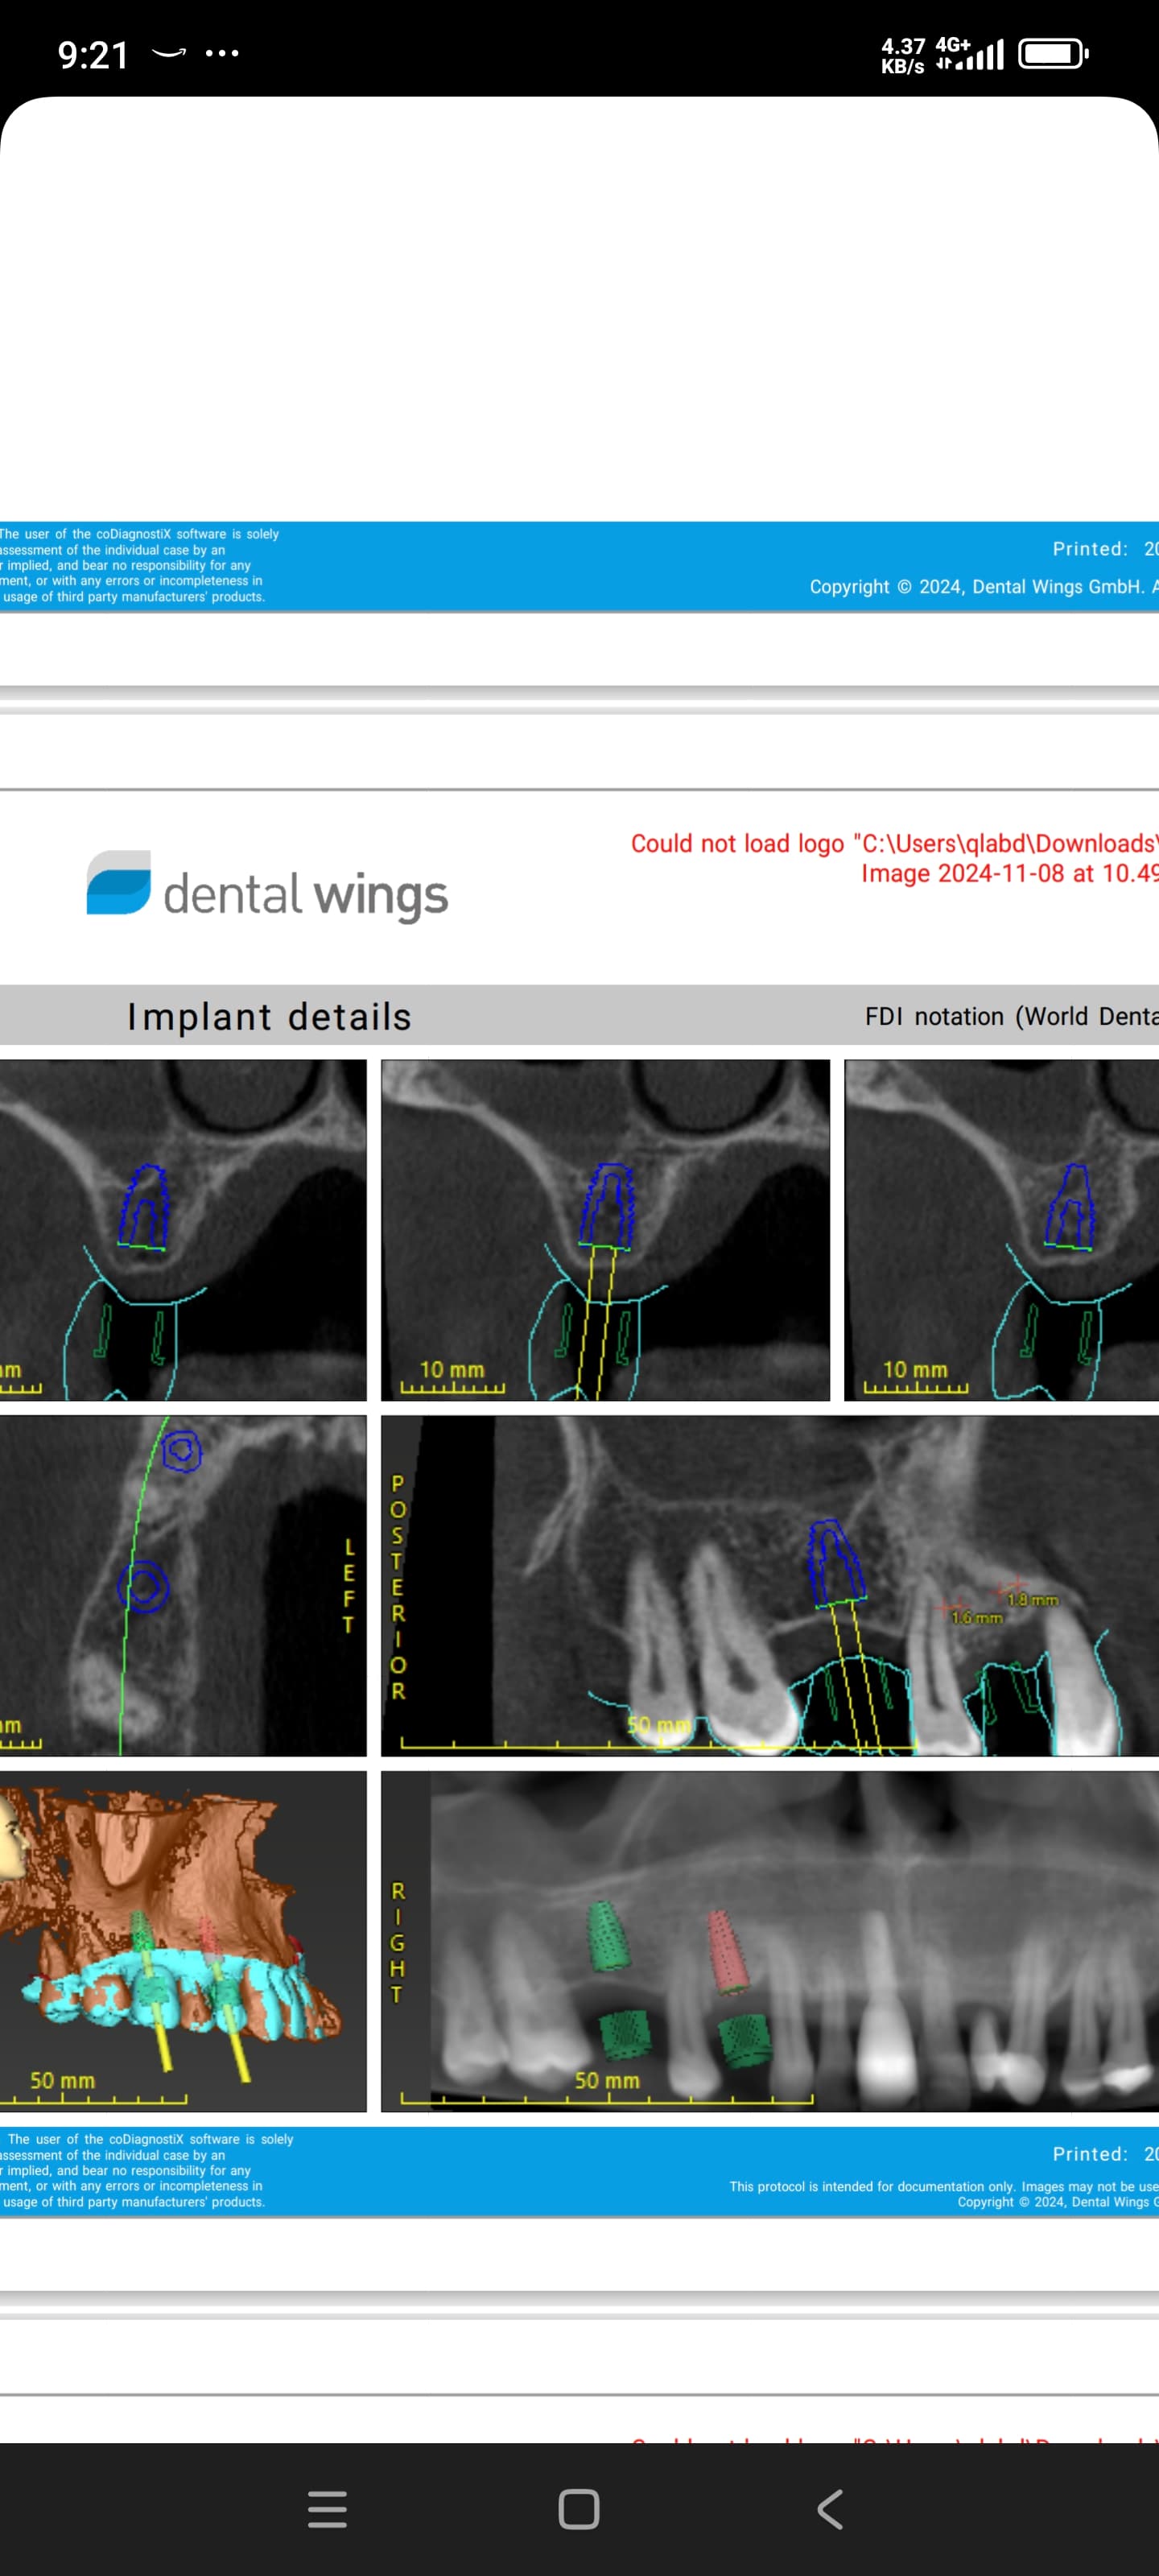

Implants placed too close: Is this restorable?

I am feeling really humble. I’ve placed multiple implants and thinking this should be a straightforward case. I was wrong. I know it’s poorly planned and freehand did not go well. Are these restorable? Should I explant and redo? If I do remove these, how easy is it to remove these?